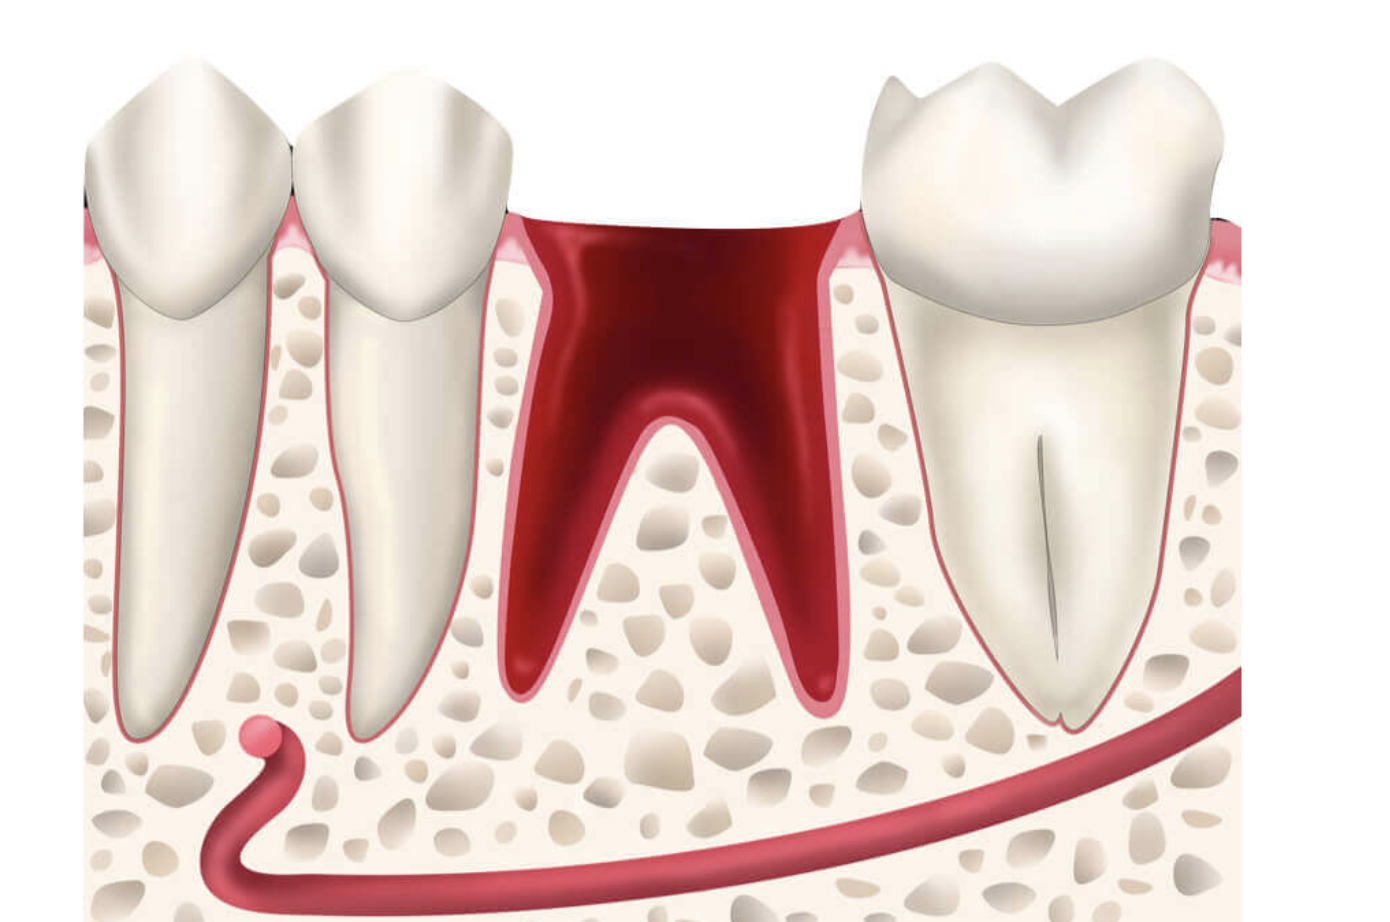

Tooth extraction